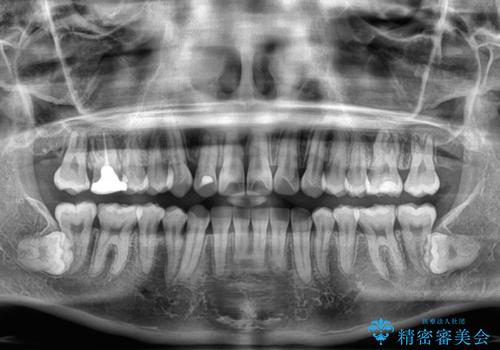

適合や携帯の悪いプラスチックのクラウンが装着されていたため、矯正治療後にオールセラミッククラウンによる補綴治療を行うこととしました。

当初予定通り1年半ほどの治療期間で、非常に綺麗な歯列に仕上げることができました。